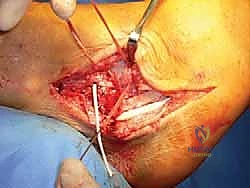

الخطوة 3: الوصول إلى المفصل وإزالة الأنسجة التالفة

يتم عمل شق جراحي مقوس على الجزء الخارجي من الكاحل. يقوم الجراح بكشف العظام (الشظية، الكاحل، الكعب) وإزالة بقايا الأربطة الممزقة والمتهالكة، وتنظيف المفصل من أي نتوءات عظمية أو التهابات مزمنة.

الخطوة 4: حفر الأنفاق العظمية (Bone Tunnels)

هذه هي المرحلة الأكثر دقة. باستخدام أدوات حفر دقيقة (Drill Guides) موجهة بالأشعة داخل غرفة العمليات، يقوم الدكتور هطيف بحفر أنفاق صغيرة جداً في المواقع التشريحية الدقيقة لمرتكزات الأربطة الأصلية: